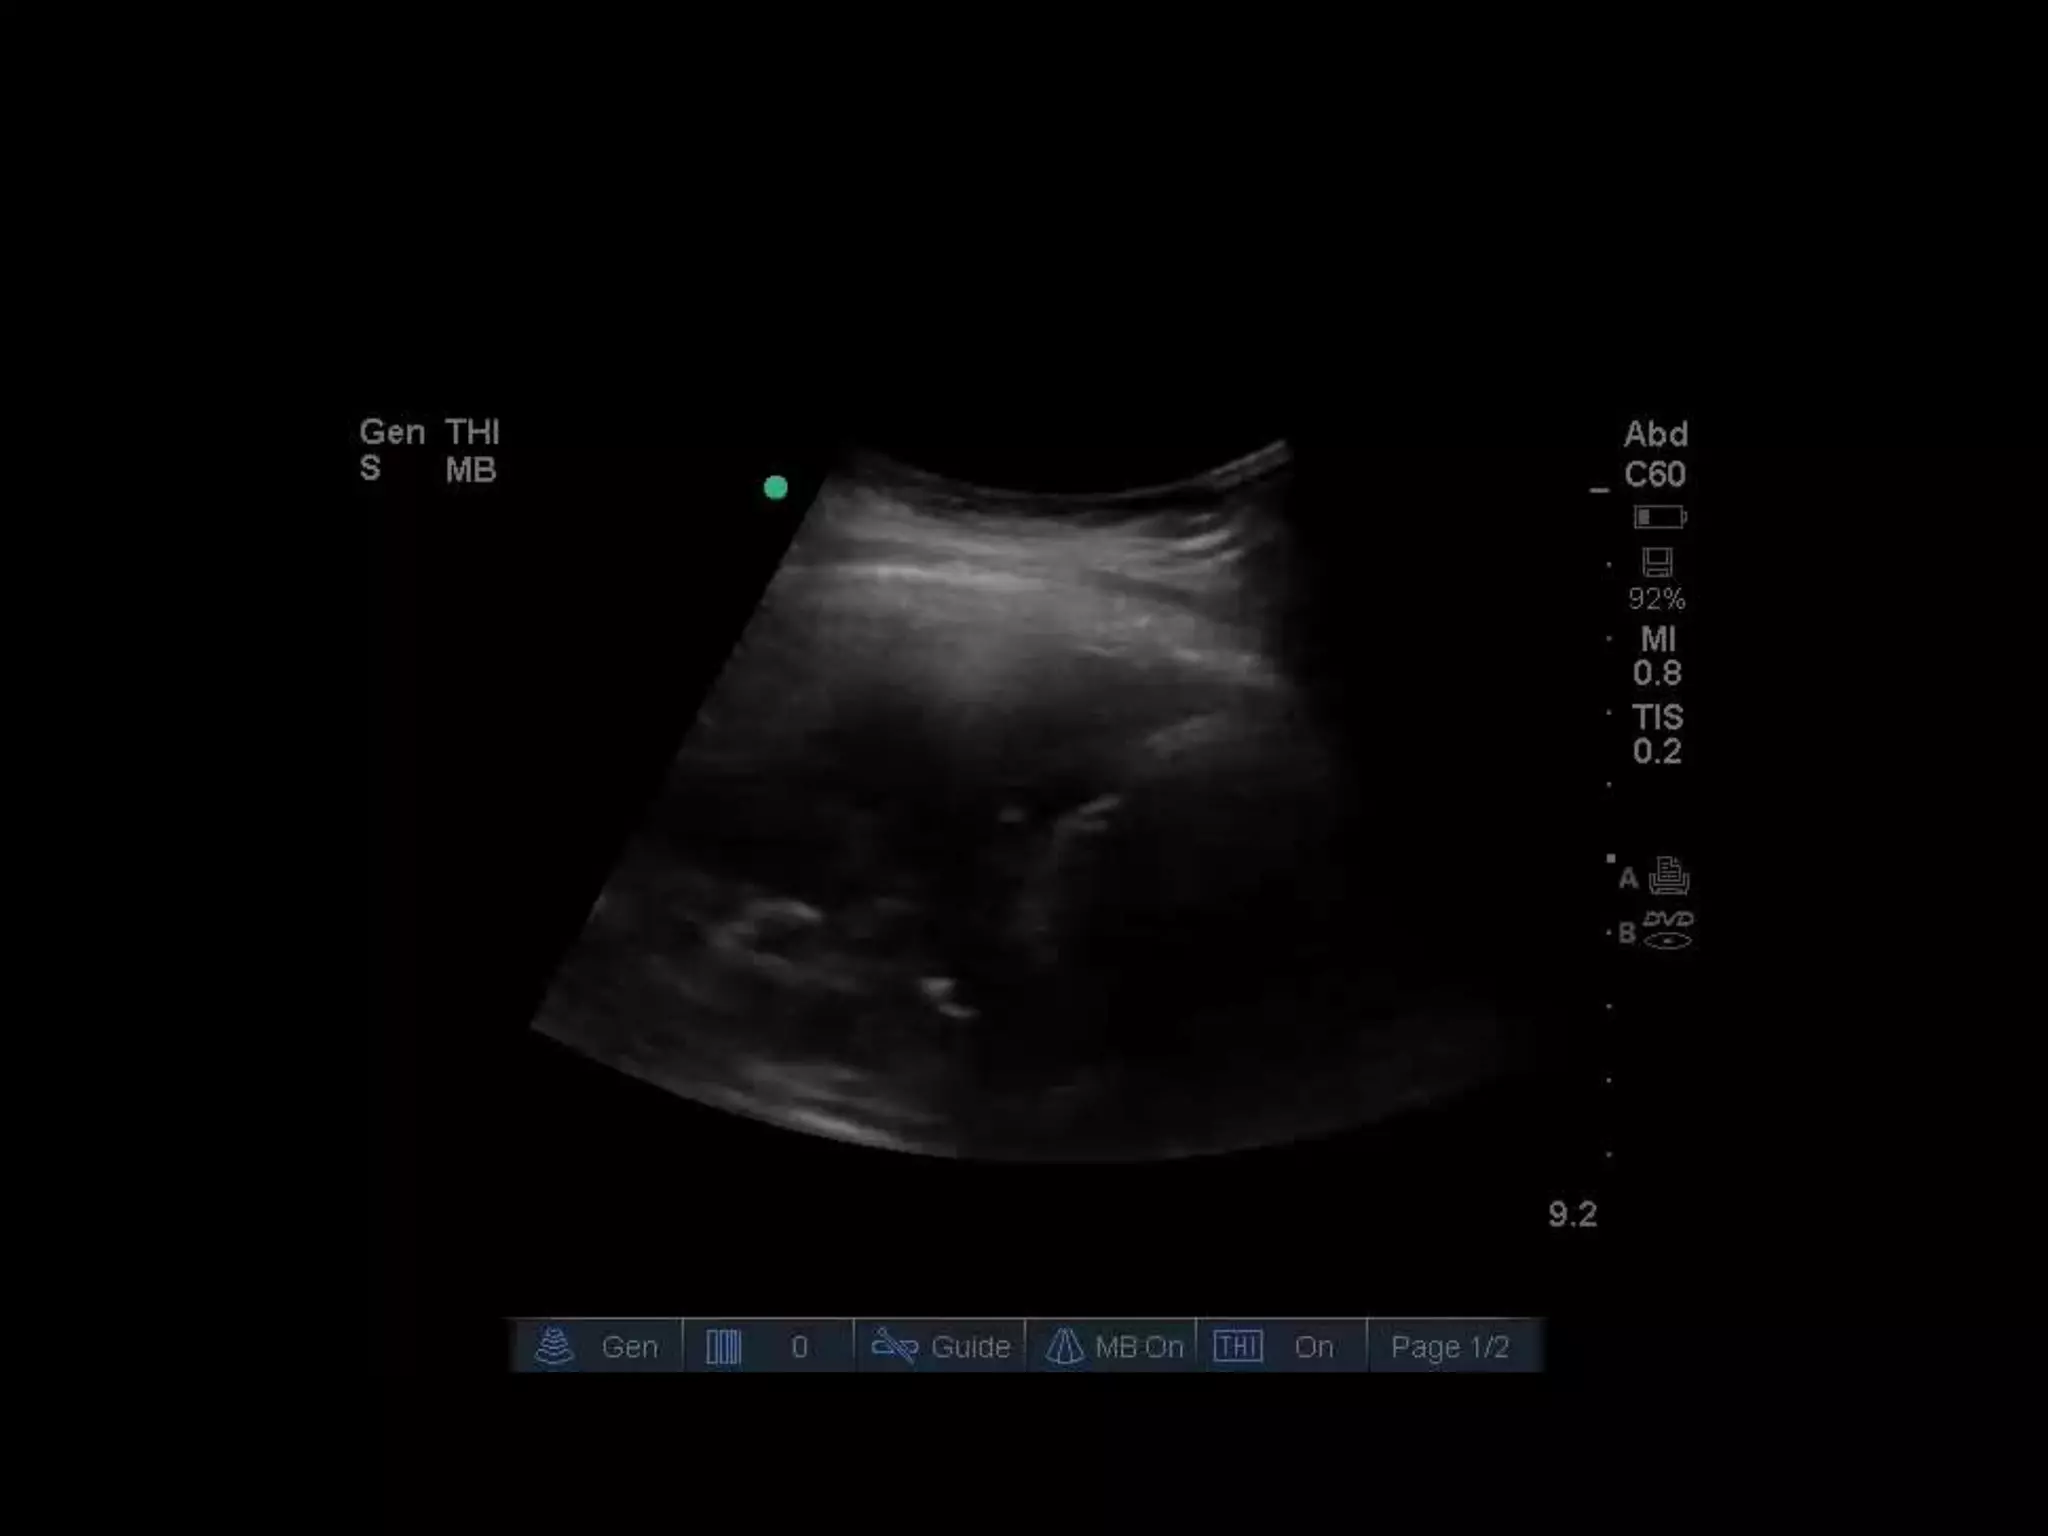

Case study 2

• Young man with history of sarcoma

• Increasing shortness of breath

• Large pleural effusion

• Fine echogenic debris suggests exudate,

infection or blood

• Nodules on pleural surfaces suggest

malignancy

• Describe spine sign and descending aorta

visualisation

• Consolidation

• Hepatisation, air bronchograms, shred sign